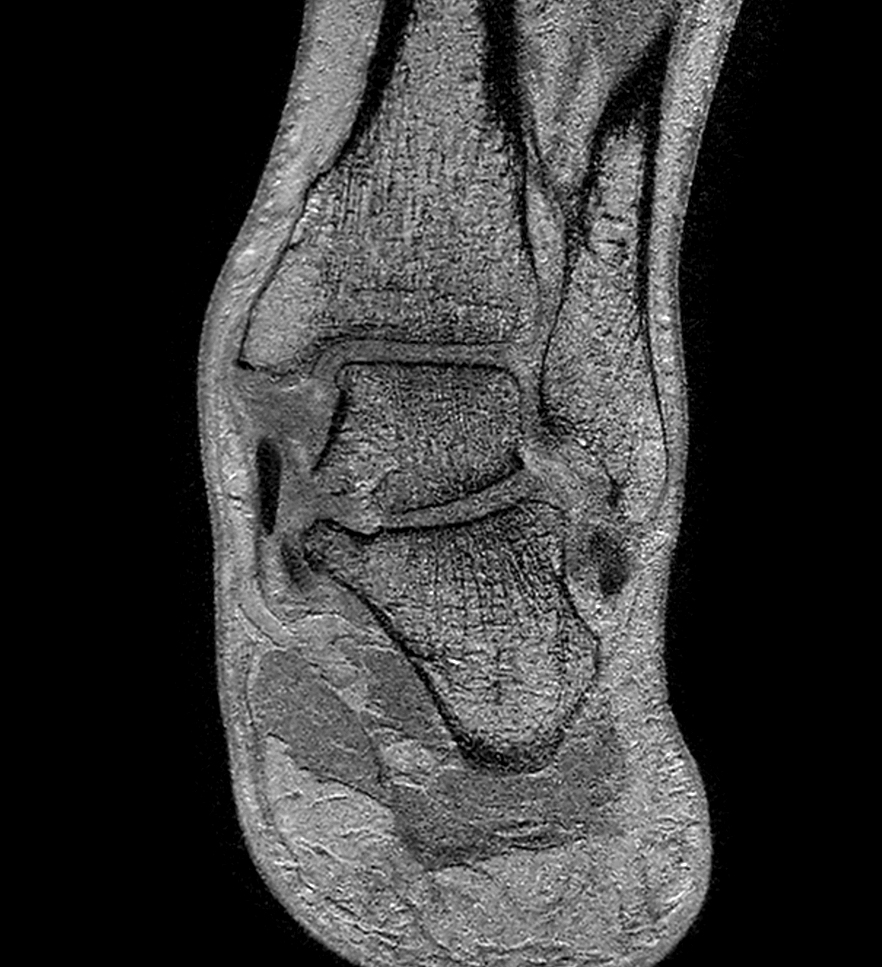

Coronal PDw mDIXON XD TSE (In Phase)

-

Coronal PDw mDIXON XD TSE (Partial FatSat)